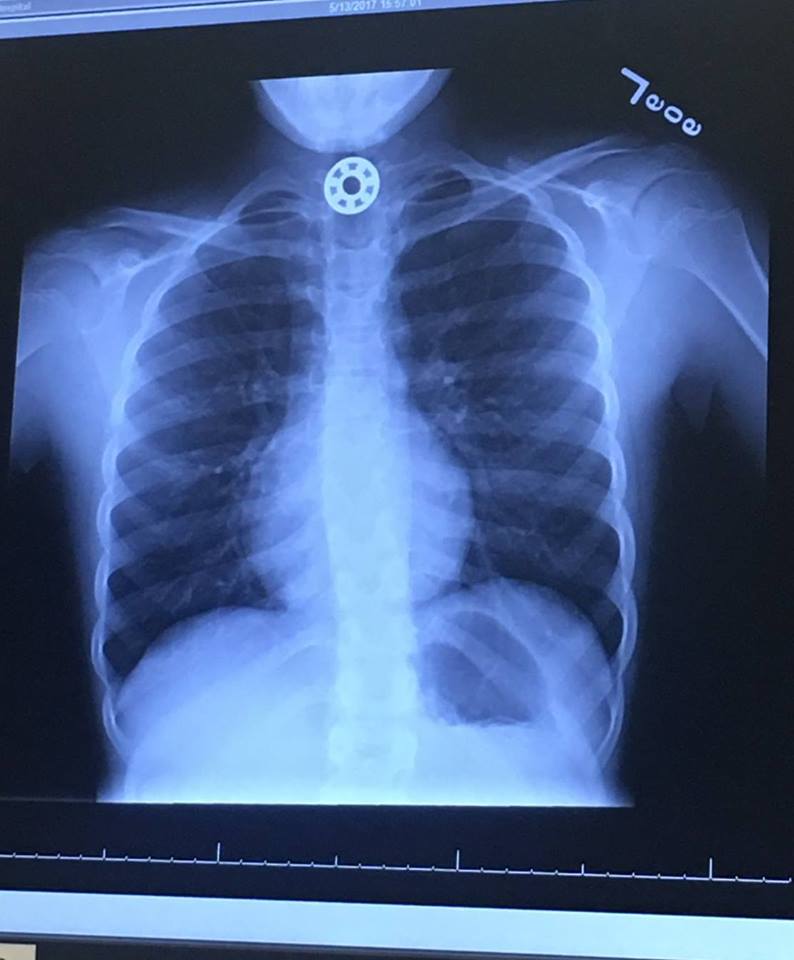

Read MoreTexas Child Swallows Piece of Fidget Spinner, Requires Medical Attention

While we already discussed the huge popularity and debatable scientific benefit of fidget spinners, news out of Texas shows that they might be downright dangerous. A Houston, Texas-area mother posted a lengthy story on Facebook about how her 10-year-old daughter swallowed a piece of her fidget spinner and had to be taken to an urgent…